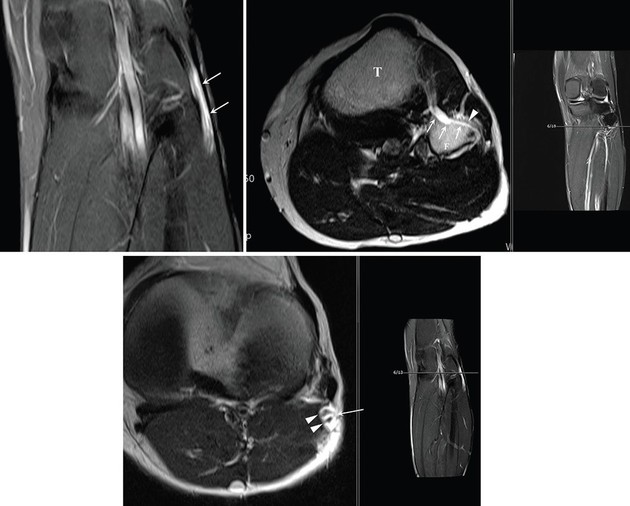

허리에서 시작하여 엉덩이 뒤쪽을 지나 다리 뒤편 허벅지, 종아리를 따라 발까지 내려가는 우리 몸에서 가장 크고 굵은 신경 다발인 좌골신경에서 발생한 희귀 난치성 양성종양 '신경내 결절종'(화살표 부분) MRI 영상 검사 사진

특히 손 교수는 해당 연구를 통해 신경곁조직 아래막 결절종이 일반적인 결절종보다 신경 섬유에 더 밀착돼 있으며, 신경 줄기를 따라 매우 광범위하고 빠르게 전이될 수 있다는 사실을 확인했다. 이러한 특성 때문에 일반적인 낭종 제거술로는 완치가 어려운 만큼, 관절과 연결된 신경 분지를 근본적으로 차단하는 정교한 수술 기법 적용이 필요할 수 있음을 제시했다.